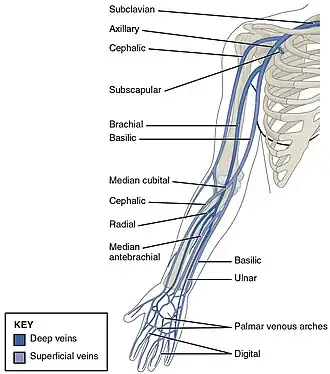

De PICC-lijn wordt in een ader in de arm aan de binnenbovenkant van de elleboog ingebracht bij een liggende patiënt: in de vena basilica (koningsader), de vena cephalica of de vena brachialis (brachiale ader). Er moet al eerder met bloedverdunners gestopt zijn. Met echoscopie wordt de loop van de aders in de arm (meestal de rechterarm) bekeken. Als de aders in de rechterarm ongeschikt zijn (bijvoorbeeld omdat ze te dun zijn) wordt voor de linkerarm gekozen. Afhankelijk van het soort slangetje kan het na meting met een rolmaat langs de patiënt op de goede lengte worden afgeknipt. Onder plaatselijke verdoving en in zo steriel mogelijke omstandigheden wordt dan de PICC-lijn na voorbereiding met een tijdelijke voerdraad (hulplijn) echogeleid ingebracht en doorgeschoven. De pleister op de ingang voor de PICC-lijn in de huid heeft een plastic schildje (Statlock of eerst een eenmalige Securacath) om het slangetje langdurig te fixeren en wordt wekelijks vervangen. De ingang van de slang die uit de arm steekt kan bijvoorbeeld aan een buisje van een infuuszak worden vastgeschroefd en worden afgesloten met een afsluitventiel (bionecteur, microvalve).[3]